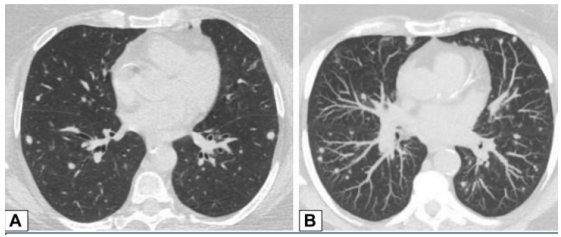

图源:Chest, 2022, 162(1):156-178.CT扫描图像显示双肺多发小实性结节(图8),提示恶性肿瘤或感染可能。CT扫描引导下针吸活检结果与OP诊断一致。图源:Chest, 2022, 162(1):156-178.42岁患者,病态肥胖,有呼吸困难,右肺上叶(图9A)和右肺下叶(图9B)CT平扫图像显示双侧、胸膜下或周围肿块样实变区域。这些发现为非特异性;活检结果提示OP,类固醇治疗后消退。图源:Chest, 2022, 162(1):156-178.OP以结节为主的影像学表现,范围从小的微结节(直径<4 mm)到较大的离散结节(直径通常达1 cm),以及较大的结节或肿块。较大的结节或肿块常被描述为具有不规则或锐利边缘,通常包含支气管充气征。图10所示为一名接受美沙拉嗪治疗的38岁男性溃疡性结肠炎患者出现气促。A为后外侧胸片,显示双肺多发结节。胸部CT增强扫描显示结节为周围型和支气管血管周围型,一些伴有气道扩张(B和C中的箭头)。粗针穿刺活检结果与OP相符。图源:Chest, 2022, 162(1):156-178.此外,结节可以单发或多发,通常为实性结节或部分实性结节。图11为一名73岁男性吸烟者低剂量CT,CT平扫图像显示右肺上叶孤立的不规则结节影,伴有细微的气道扩张(A中箭头)。支气管内超声引导下细针活检结果符合局灶性OP表现。图源:Chest, 2022, 162(1):156-178.临床中遇到影像学表现为结节的情况,需要注意与肿瘤相鉴别。PET扫描对这些病变的评估显示标准化摄取值轻微升高,但结果为非特异性,临床价值有限。图12所示为PET扫描一名无症状、有乳腺癌病史并长期使用呋喃妥因的70岁女性,CT平扫图像显示双肺下叶不规则、实性结节。由于担心转移性疾病,进行了PET扫描(图12C),轴位PET图像显示左肺下叶结节(B、C中箭头)是FDG高摄取。左肺下叶结节的粗针穿刺活检结果与OP相符。图源:Chest, 2022, 162(1):156-178.34岁女性患者因系统性红斑狼疮就诊,表现为气促。胸部CT显示双肺多发大小不等的实性结节,包括左肺基底部微小结节改变(图13A)。FDG-PET扫描的图像显示结节为高代谢(图13B)。两个结节的楔形活检结果符合OP诊断。图源:Chest, 2022, 162(1):156-178.以线状或网状为主的OP影像特点包括表现为线状不透明的实质条带,通常延伸到胸膜表面,先于磨玻璃影或实变。图14所示为条带活检证实为OP的同一患者间隔1年进行的CT扫描,可见患者双肺下叶条带部分消退(A、B中箭头)。

图14 实质条带

图源:Chest, 2022, 162(1):156-178.其他表现还包括小叶周围增厚和具有反晕外观特征的病变(环礁征)。图15所示为一名慢性持续性咳嗽和劳力性呼吸困难1年、体重减轻的32岁男性患者的CT图像,双侧中心磨玻璃样病灶完全被周围致密实变所包围,即反晕征或环礁征(A、B中红色箭头)。也存在不完全晕征(A、B中白色箭头)和小叶周围增厚(B中黄色箭头)。肺活检结果证实为OP。图源:Chest, 2022, 162(1):156-178.当以线性或网状为主的OP进一步发展,在周围实变或磨玻璃影后,基底和胸膜下网状形成,提示间质纤维化的发展。图16为一名73岁男性患者在呼吸困难发作4 d后获得的CT图像,分别在隆突水平(A,C)和以及肺基底水平(B,D)获得胸部CT图像。2019年的增强图像(A和B)显示双侧广泛的磨玻璃影;2021年的图像(C和D)显示磨玻璃影程度改善,但出现网状和牵拉性支气管扩张或细支气管扩张,这一模式与纤维化相符。右肺上、中、下叶的楔形活检结果显示OP。图源:Chest, 2022, 162(1):156-178.OP可导致广泛的双基底牵引性支气管扩张,其结果与非特异性间质性肺炎(NSIP)相似,并经常重叠。图17为51岁女性皮肌炎患者CT平扫图像,下肺基底图像显示双肺下叶实变,双侧胸膜下和磨玻璃影。矢状位图像上支气管明显扩张(B)。这些表现与OP和NSIP重叠一致。图源:Chest, 2022, 162(1):156-178.一名病态肥胖且进行性呼吸困难的67岁男性患者进行了CT扫描(图18)。肺基底部CT显示周围支气管壁增厚,伴有边界不清的磨玻璃密度和小叶周围增厚,特别是在左基底部(箭头),这些表现提示NSIP。外科肺活检结果与OP相符。